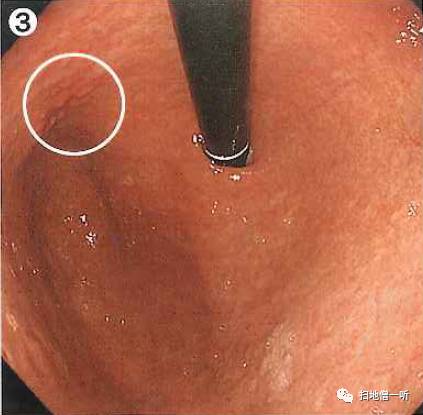

A:胃癌在图3及图6。HP未感染胃癌。

胃粘膜RAC阳性表现,提示HP未感染粘膜。胃体下部小弯侧可见小片状褪色粘膜。图3和图6是两个角度观察同一处病变。

靛胭脂喷洒然后后边界不清,表面无凸凹变化,为IIb型病变。无萎缩的胃底腺区域发现退色调病变,应怀疑印戒细胞癌。

最终病理诊断:

胃体下部小弯,O-IIb,4mm,sig,T1a (M),UL(-)

小结:HP未感染背景下退色调病变应注意着重观察。

其他图片补充说明:

图1可见胃窦部条带形发红,靛胭脂染色后更加清晰,被定义为术语:条带状发红,此为HP阴性所见粘膜像。

胃体上部大弯侧可见山田II型胃底腺息肉,边界清晰,表面光滑,此亦提示HP阴性粘膜征象。